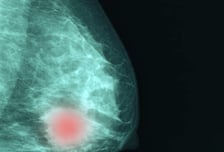

유방암이 간으로 이동하는 기전 韓의료진이 밝혀…표적치료 근간 될까

유방암이 간(肝)으로 전이되는 '유방암 간 전이' 과정의 새로운 메커니즘을 규명한 연구 결과가 국내에서 나왔다. 서울대병원 유방센터 문형곤 교수팀(허우행 연구원)은 한국인 유방암 환자의 암조직을 면역이 억제된 쥐에 이식해 종양을 키운 '환자 유래 이종이식 모델'(patient-derived xenograft model, PDX model)을 이용한 동물실험에서, 유방암이 간까지 전이되는 기전을 연구로 규명했다고 9일 발표했다. 유방암은 2023년 세계 여성암 발생률 1위, 사망률 2위로 무서운 질환이다. 유방암으로 인한 사망률은 대부분 유방암 환자의 원격 전이(원발 부위의 암보다는 폐·간·뼈 등 다른 장기로 전이된 경우)로 인해 발생한다. 간은 유방암 환자에게 두 번째로 흔한 원격 전이 부위다. 국내 유방암 환자의 생존 자료를 분석한 2016년 연구에 따르면 간 전이는 뼈·폐 전이보다 치료하기 힘든 데다, 환자의 생존 기간도 비교적 짧다. 이러한 유방암 간 전이의 임상적 중요성에